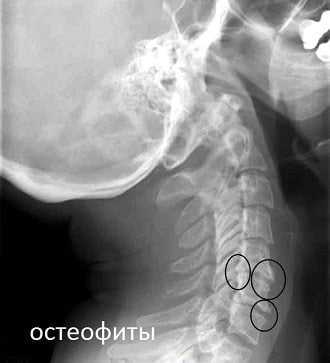

Что касается патогенеза ангиовертеброгенной лабиринтопатии, то в основе его, вероятно, лежат различные сочетания лабиринтных (периферических) и центральных ангиодистонических явлений, приводящих к нарушению кровообращения в указанных структурах. Причинами этих нарушений могут быть механические сдавления экстракраниальных отделов позвоночной артерии остеофитами или суставными отростками, сужение просвета артерий атеросклеротическими бляшками, патологическими изгибами и т. д.

- сформировавшиеся остеофиты (острые костные наросты) сдавливают позвоночную артерию, что приводит к снижению объема крови, поступающей в головной мозг;

- рентгенография шейного отдела в прямой и боковой поверхности для выявления признаков остеохондроза;